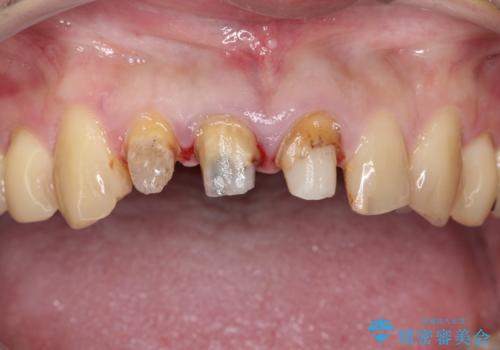

- 前歯のかぶせ物を自然な色味のものにしたいとのことで、来院されました。

保険適用のかぶせ物が装着されており、適合も悪く、変色している状態でした。

土台からの、再治療を行い、オールセラミッククラウンの装着を行う計画としました。